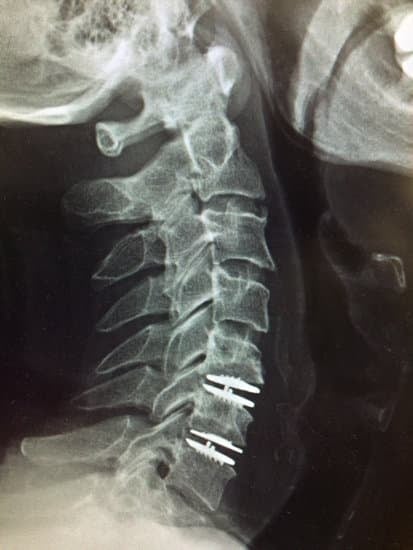

경추 인공디스크 치환술

경추 인공디스크 치환술은 경추 디스크 질환으로 인한 통증과 다른 증상을 완화하기 위해 수행되는 수술입니다.

수술 중에는 손상된 디스크를 제거하고, 인공디스크를 삽입하여 디스크의 기능을 대체합니다.

4. 인공디스크 삽입

손상된 디스크를 제거한 후, 측정과 평가를 통해 환자에게 가장 적합한 인공디스크를 선정합니다.

이 인공디스크는 경추의 자연스러운 움직임을 모방하도록 설계되었으며, 삽입 과정은 정밀하게 수행됩니다.